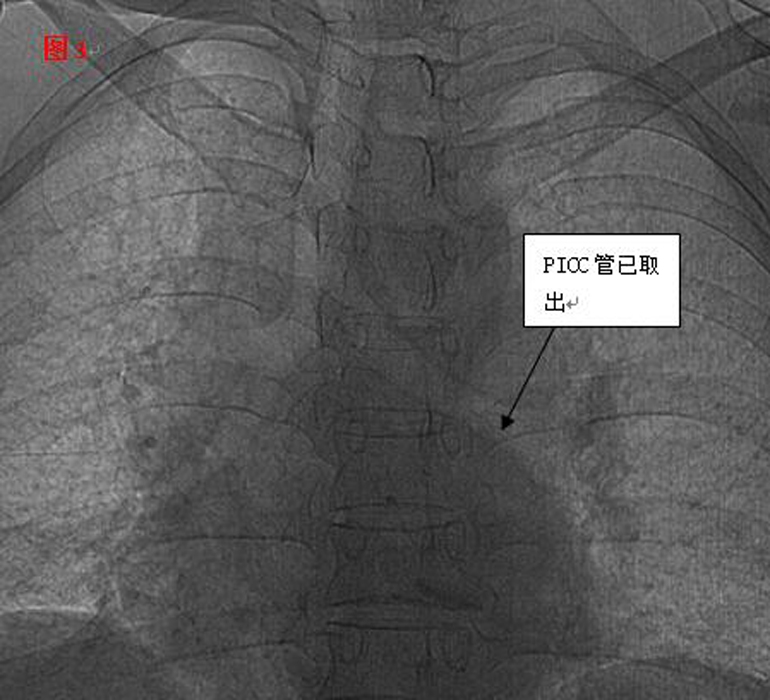

??? 憑借醫(yī)師的高超技術(shù)加上團隊的密切合作,手術(shù)圓滿成功,30厘米的導管被完整取出,術(shù)后復查未見殘留。當手術(shù)結(jié)束的那一刻,躺在手術(shù)臺上的麗琴由衷的感謝聲,以及在場觀摩學習人員的掌聲,讓手術(shù)室內(nèi)格外溫情。